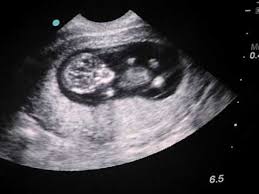

At 11 13 weeks all babies are believed to have a nub between their legs called the genital tubercle and according to the nub theory the angle indicates the baby s sex. The genitalia of a toddler would not even form till around week 12. If you have a prenatal blood test nipt you may be able to find out your baby s sex as early as 11 weeks of pregnancy. This theory says you can predict your baby s sex 26 weeks before conception based on the mum s blood pressure.

January 16 2020 at 11 30 am. So once those hormones kick in the genital ridge begins differentiating into these structures. The gender of your baby is revealed at your second scan between 18 and 21 weeks but there s another test people use to determine if it s a boy or girl credit. If the nub is pointing up at an angle it s likely to be a boy and if it s parallel to the spine chances are better that it s a girl.

So at thirteen weeks boys and girls will nonetheless look quite lots the comparable. For most fetuses with xy chromosomes the genital ridge starts to lengthen into a penis by week 11. At 12 weeks boys and girls look the same. Maximum medical doctors do not do the gender ultrasound till around 18 20 weeks besides with the aid of fact doing one earlier than which could consequence in a incorrect gender.

While both procedures carry risks they are extremely accurate in making the determination and can return a result by as early as week 11 for cvs and week 15 for amniocentesis. Tiny buds will form the prostate around week 14 and the urinary system is formed by week 16. At 12 weeks gestation the accuracy was 94 8 percent and at 13 weeks it was 98 3 percent with the accuracy being slightly higher in determining boys than girls. I have a photo at 13 weeks that i thought my girl twin was a boy.

4 weeks later she was clearly a girl. She reckons you can tell by the way your hands are when you cup the side of your bump. It s said that if the nub is over 30 degrees up from the spine it s a boy but if it s under that then it s a girl. It s not totally reliable as the tech told me girl at that point and at 18 weeks he was most definitely a boy.